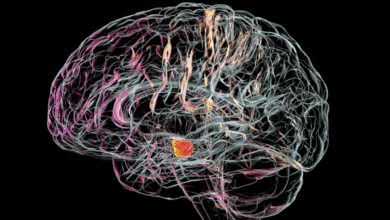

تجربة علاجية صينية تعيد الأمل لمرضى باركنسون حول العالم

طوّر باحثون صينيون علاجا تجريبيا جديدا لمرض باركنسون، يعتمد على الخلايا الجذعية، أظهر نتائج واعدة في تحسين أعراض المرض لدى…

مؤشر جديد لمرض باركنسون

ذكرت مجلة Annals of Neurology أن دراسة أجرتها مجموعة دولية من العلماء، كشفت عن مؤشر قد يدل على الإصابة بمرض…